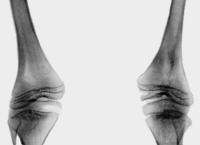

Рентгенологически у больных диастрофической дисплазией определяется уменьшение относительной длины трубчатых костей конечностей, часто сочетающееся с их дугообразной деформацией. Выявляются расширение метафизов, деформация головок бедренных костей, подвывихи и вывихи крупных суставов (коленных, локтевых, тазобедренных). Пястные кости и фаланги пальцев нередко укорочены, аналогичные изменения просматриваются и на костях плюсны. Практически всегда при диастрофической дисплазии обнаруживаются искривления позвоночника - сколиоз и кифоз различной степени выраженности. Молекулярно-генетическая диагностика заболевания сводится к прямому секвенированию гена SLC26A2 с целью подтверждения характерных генетических дефектов. Этот метод позволяет наиболее точно дифференцировать диастрофическую дисплазию от других скелетных аномалий, обусловленных мутациями SLC26A2.